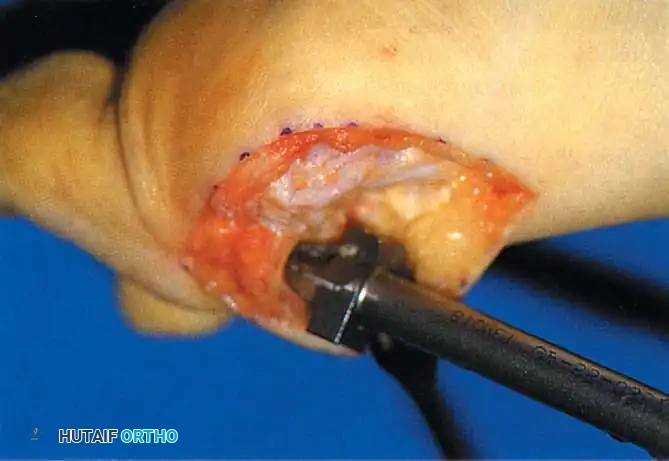

• Using a Freer elevator or a small osteotome for its strength, mobilize the fi bular sesamoid (Fig. 78-31A to C). This may be diffi cult in elderly patients with signifi cant deformity and adherence of the sesamoid to the metatarsal head. Lift the metatarsal dorsally for exposure (Fig. 78-31D and E).

Fig. 78-31 Excision of fi bular sesamoid in modifi ed Keller procedure. With base of proximal phalanx removed and medial eminence excision, exposure of fi bular sesamoid is not as diffi cult from medial incision. A, Operative photograph showing elevation of fi rst metatarsal with strong two-tooth retractor and use of small osteotome to mobilize fi bular sesamoid and lateral capsuloligamentous (frequently contracted) structures. Osteotome is between metatarsal head and lateral sesamoid. When mobilization of fi bular sesamoid is complete, entire sesamoid is visible for excision. Note chondromalacia of tibial sesamoid articular surface medial to osteotome. B, Fibular sesamoid has been excised, and lateral capsular structures and conjoined tendon (in forceps) have been released. Neurovascular bundle to lateral side of hallux is adjacent to these structures. C, Diagrammatic representation of modifi ed Keller procedure. By excising fi bular sesamoid, valgus moment of conjoined tendon of fl exor hallucis brevis and adductor hallucis no longer pulls fl exor hallucis longus tendon laterally (carrying hallux with it) through capsulosesamoid plantar plate and pulley system. D, Metatarsal head must be lifted dorsally to excise fi bular sesamoid under direct vision. E, Note exposure of fi bular sesamoid after mobilization of metatarsal head. Continued